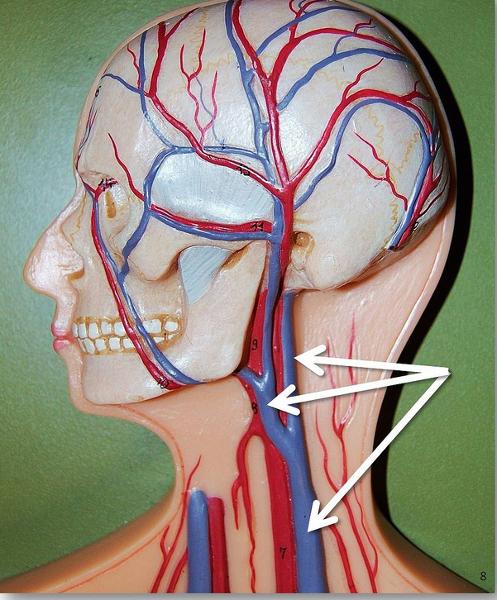

Internal/external/common carotid artery

internal/external/common jugular vein

Vertebral artery